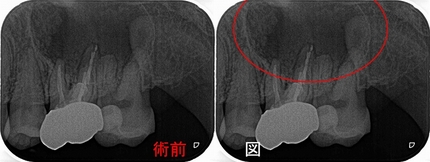

2025 EEdental TUT (5).jpg

2025 EEdental TUT (6).jpg

病変はかなり小さくなり、病変があった部分の副鼻腔の所見も戻ってきてくれています。

とりあえず、もう半年待って経過観察しましょうと説明させてもらいました。